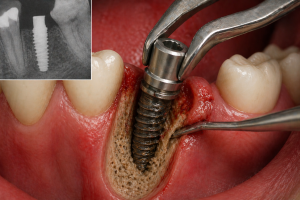

CÓMO EXTRAER UN IMPLANTE DENTAL Soluciones seguras y mínimamente invasivas LA CLAVE PARA IDENTIFICAR IMPLANTES. La retirada de un implante dental puede convertirse en un...

CÓMO EXTRAER UN IMPLANTE DENTAL Soluciones seguras y mínimamente invasivas LA CLAVE PARA IDENTIFICAR IMPLANTES. La retirada de un implante...